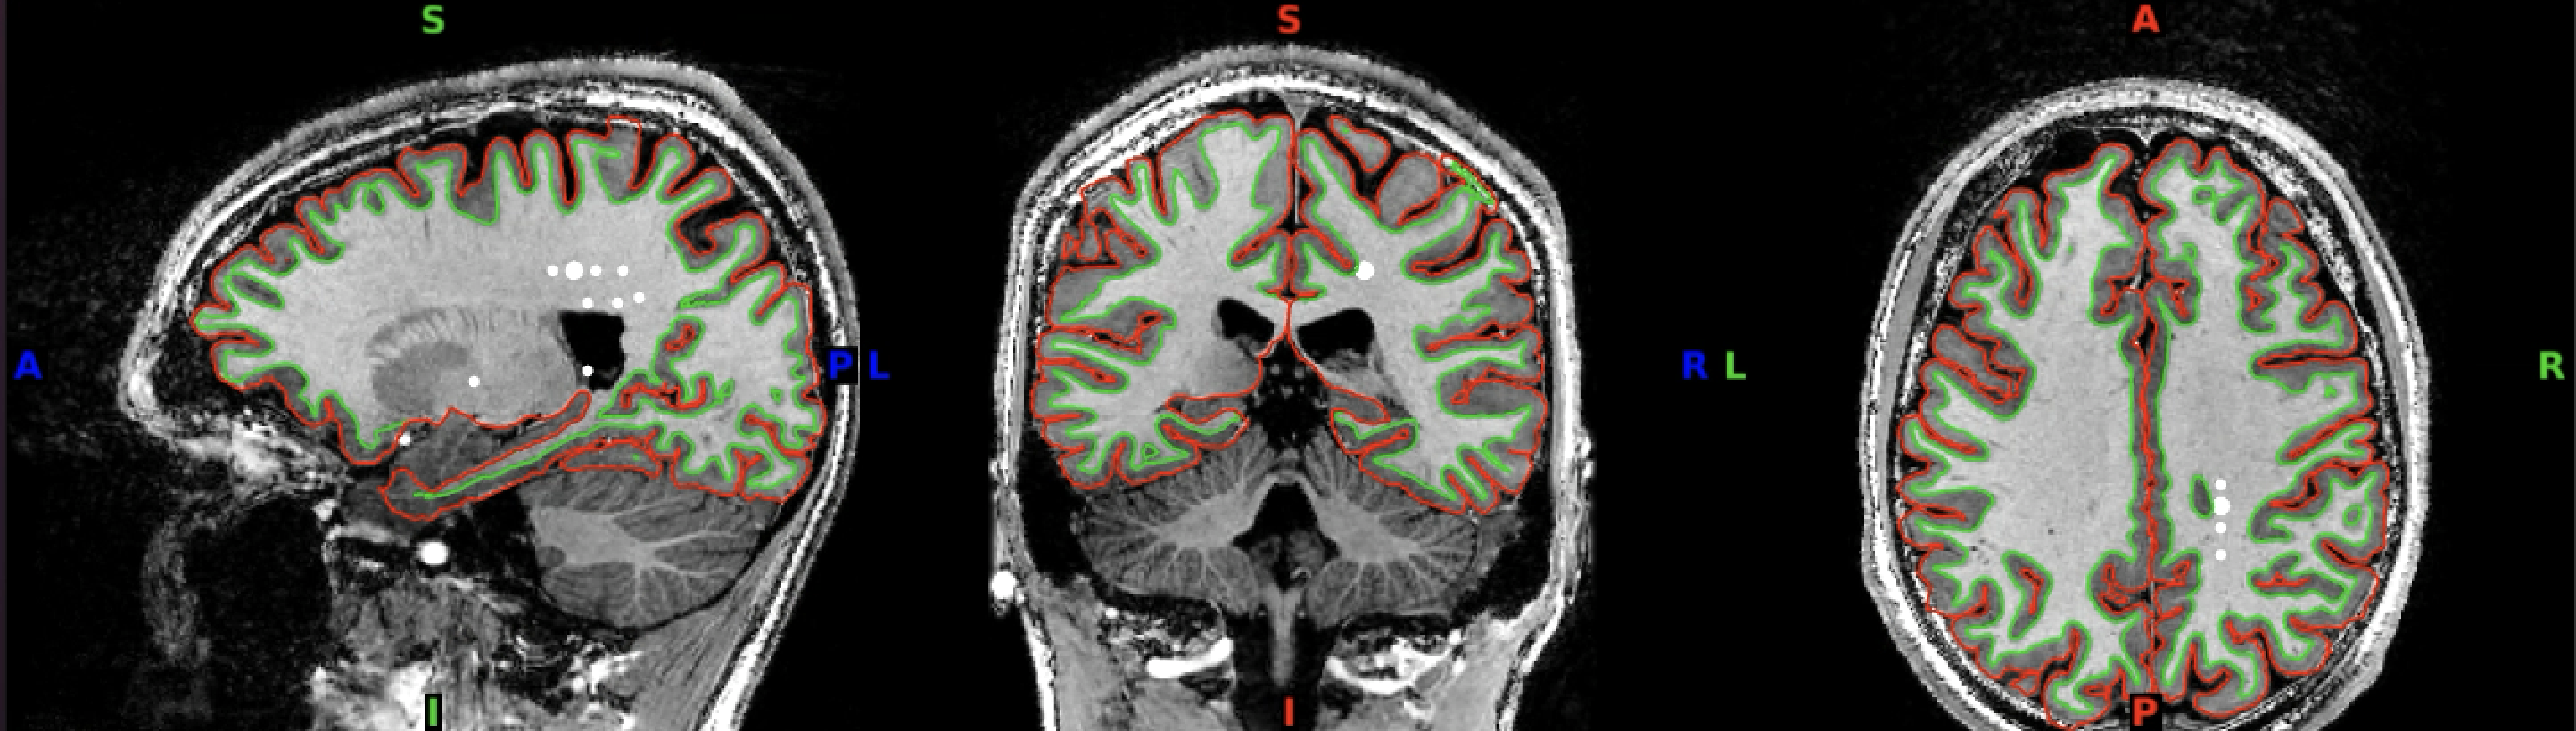

For a different view of the surfaces, inspect the outline of the surface reconstructions in 2D. For this, load both the white matter and the pial surfaces into wb_view along with the T1. Click on ‘Volume’ view and ‘All’ to see the axial, coronal and saggital slices.

Then, click on the pial and white matter surfaces and select red for the pial surface and lime for the white matter surface.

If you have selected these surfaces to be visible, you should now see something like this:

You can click through the volume and see if you spot any faulty reconstructions. In the below example, the right hemisphere has been misconstructed. Both white and pial surfaces are going into the skull on the right side. This will lead to wrong projections of the functional data - in this case, there was a chunk of ‘NaN’ values in the superior right hemisphere.